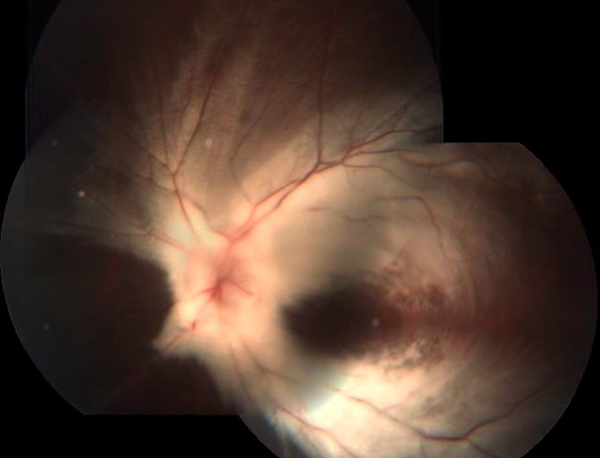

Figura 2:

Fundoscopía OS, con FNM sobre arcadas vasculares nasales y temporales que involucran el área macular

A la exploración oftalmológica presenta agudeza visual (AV) en el ojo derecho (OD) de 20/30, en el ojo izquierdo (OI) de 3/200 con una capacidad visual (CV) en 20/20, 20/400 respectivamente. A la esquiascopía con una refracción en el OD -1.00=- 1.50x180º y en el OI: -10.00=-4.50x180º. A la biomicroscopía de segmento anterior sin alteraciones en ambos ojos (AO) con una presión intraocular (PIO) por tonometría de Goldmann de 14 y 15 mmHg, respectivamente. A la fundoscopía OD sin alteraciones (Fig. 1). En el OI presenta retina aplicada, excavación no valorable por la presencia de fibras nerviosas mielinizadas sobre arcadas vasculares nasales y temporales que involucran el área macular (Fig. 2).